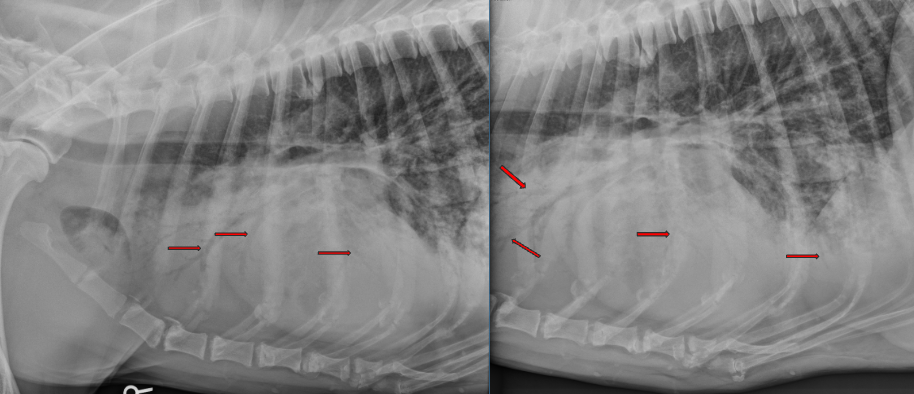

Stifle DJD (likely from a cruciate ligament rupture)

intracapsular swelling (cranial displacement of infra patellar fat pad and caudal displacement of fascial stripe)

What are 4 common osteophyte locations for stifle DJD?

apex of the patella

trochlear groove

medial and lateral aspects of the distal femur and proximal tibia

fabellae